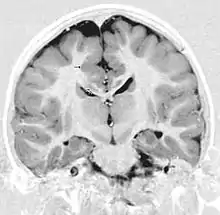

Gray matter heterotopia

Gray matter heterotopia is a neurological disorder caused by gray matter being located in an atypical location in the brain.[1]

Grey matter heterotopia is characterized as a type of focal cortical dysplasia. The neurons in heterotopia are otherwise healthy; nuclear studies have shown glucose metabolism equal to that of normally positioned gray matter.[2] The condition causes a variety of symptoms, but usually includes some degree of epilepsy or recurring seizures, and often affects the brain's ability to function.